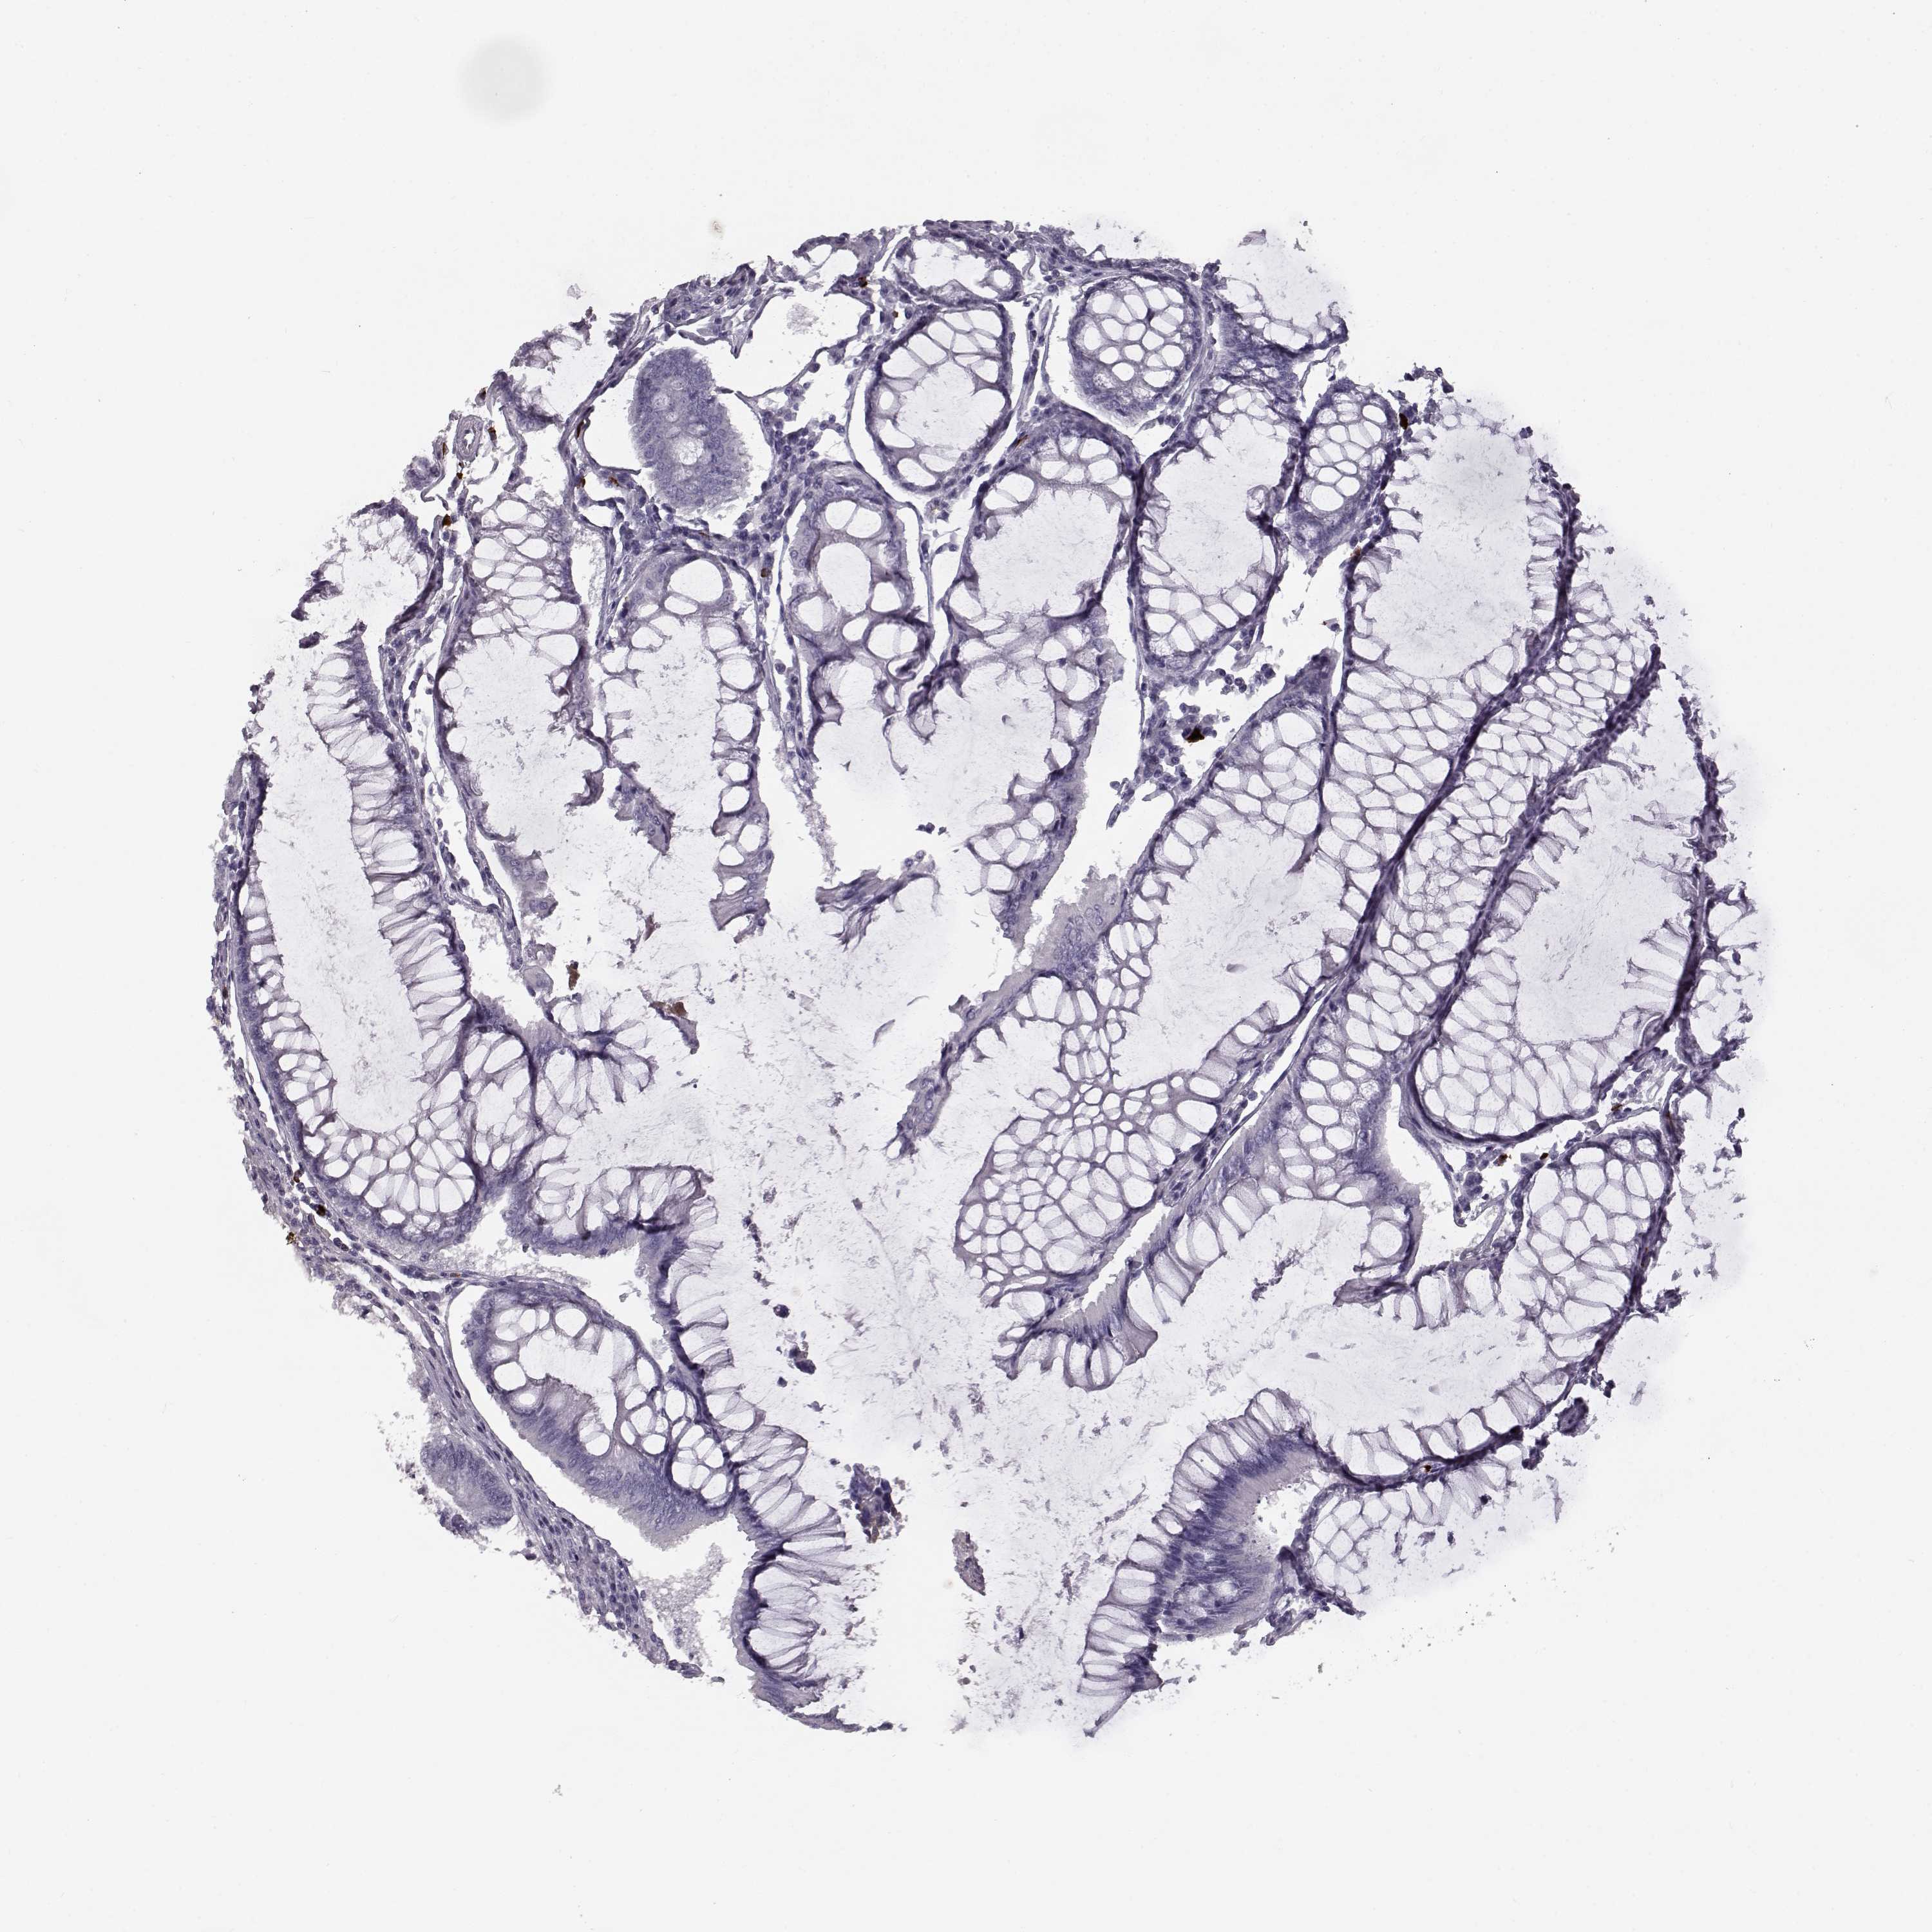

CANCER COLORECTAL CANCER Show tissue menu

Colorectal cancer

Human cancer

Colon adenocarcinoma